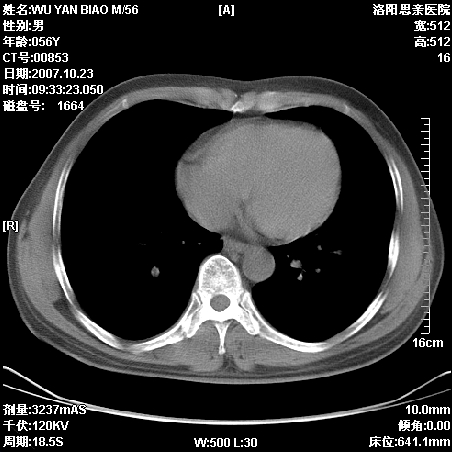

标题: CT10160:M56Y,体检发现,病人无不适,病人随访中 [打印本页]

标题: CT10160:M56Y,体检发现,病人无不适,病人随访中

后上纵隔占位,与肺交界清,宽基底附着脊柱,密度均匀,局部骨质无明确改变.

考虑;神经源性肿瘤,---起源交感n链?,不除外肠源性囊肿.

后纵隔神经原性肿瘤可能性大,孤立性胸膜间皮瘤待排.

1、病灶在后纵隔脊柱旁沟内,此处是神经原性肿瘤的好发部位

2、病灶边缘光滑整齐,更说明病灶来于纵隔,由于有胸膜的包裹所以才导致这么光滑的边缘

3、病灶内的密度均匀